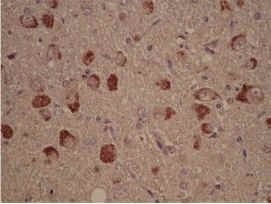

IHC-P analysis of granular lesions in the hippocampus of a patient with Alzheimer's disease tissue using GTX10877 Casein Kinase 1 delta antibody.